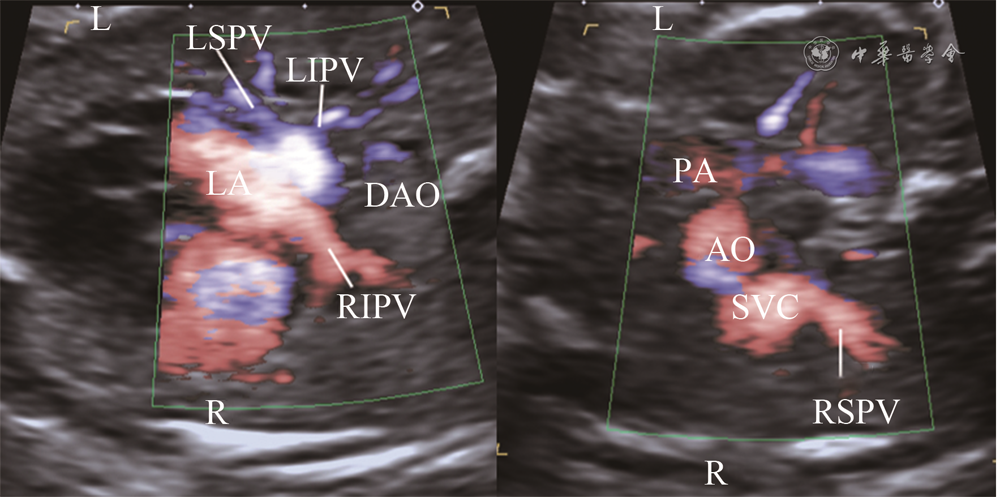

图1 正常胎儿肺静脉区域血流分布超声图像。左图白线将胸部横切面肺组织大致分为4个区域,左侧前上部1/2肺野、左侧后下部1/2肺野、右侧前上部1/2肺野、右侧后下部1/2肺野;右图彩色血流显示左上肺静脉远端分支分布于左侧前部1/2肺野,左下肺静脉远端分支分布于左侧后部1/2肺野,右上肺静脉远端分支分布于右侧前部1/2肺野,右下肺静脉远端分支分布于右侧后部1/2肺野(对应动态图1),4条肺静脉近心端呈螃蟹征插入左侧心房壁,分支间距较大

动态图1 正常胎儿肺静脉区域血流分布超声动态图像

2015至2019年共完成19 372例胎儿的超声心动图检查,检出41例(0.2%)APVD胎儿(不合并其他心内畸形)。41例APVD胎儿中,TAPVD 36例(心上型25例,心内型7例,心下型2例,混合型2例),PAPVD 5例。在胸部横切面上,41例胎儿肺静脉均显示,显示率为100%;左侧前上部1/2肺野、左侧后下部1/2肺野、右侧前上部1/2肺野、右侧后下部1/2肺野肺静脉远端分支分别引流入左上肺静脉、左下肺静脉、右上肺静脉、右下肺静脉。

临床工作中,鉴别胎儿肺静脉回流正常还是异常,诊断胎儿APVD是完全型还是部分型,首先需要对肺静脉分支进行辨认。既往研究对肺静脉分支的超声定位多以正常成人肺静脉近心端为观察点。何怡华等5应用超声观察正常成人右上肺静脉开口紧邻房间隔,近端与上腔静脉相邻;右下肺静脉相对于右上肺静脉稍远离房间隔,位于右侧;左上肺静脉紧邻左心耳;左下肺静脉相对于左上肺静脉远离左心耳,靠近胸降主动脉。但是由于胎儿体位多变、肺静脉分支变异等因素,仅使用近心端位置定位肺静脉分支往往产生错误的判断,导致肺静脉分支不能得到全面的检查,继而发生漏诊、误诊;另外APVD胎儿肺静脉近心端位置常常发生变化,有时不能用来对分支进行定位。胎儿肺组织内没有气体,因此为超声观察肺静脉远心端提供了良好的透声窗,使用彩色血流尤其是对低速血流敏感的彩色多普勒血流显像技术如e-Flow、ADF、HDFI、能量多普勒等6, 7, 8,能够使肺静脉远心端显像。本研究应用区域血流追踪法观察肺静脉,将肺组织大致分为4个区域,主要依据为肺静脉分支解剖。通常人体有4根肺静脉从心脏后部汇入左心房,即左上肺静脉、左下肺静脉、右上肺静脉、右下肺静脉;左上肺静脉收集左肺上叶的静脉血,属支包括尖后段、前段和舌段静脉干;左下肺静脉收集左肺下叶的静脉血,由上段和底段总静脉构成;右上肺静脉收集右肺上叶和中叶的静脉血,由上叶和中叶静脉汇合而成,右上叶静脉属支包括尖段、前段及后段静脉,右中叶静脉属支包括外侧段和内侧段静脉;右下肺静脉收集右肺下叶的血液,由上段和底段总静脉汇合而成9。因此,应用彩色血流技术可以观察到41例APVD胎儿肺组织4大区域(左侧前上、左侧后下、右侧前上、右侧后下部1/2肺野)肺静脉血流分别引流入左上肺静脉、左下肺静脉、右上肺静脉、右下肺静脉,这与正常胎儿是相同的。应用区域血流追踪法观察肺静脉分支回流区域,使得胎儿期肺静脉分支定位更加准确、更加全面,不容易受肺静脉近心端变异或引流部位异常的影响。不足的是,由于胎儿肺静脉细小,肺静脉分支属支不能完全显示,因此没有对其属支进行细致的划分,目前仅做了大致的区域划分,但其可作为今后研究的方向。